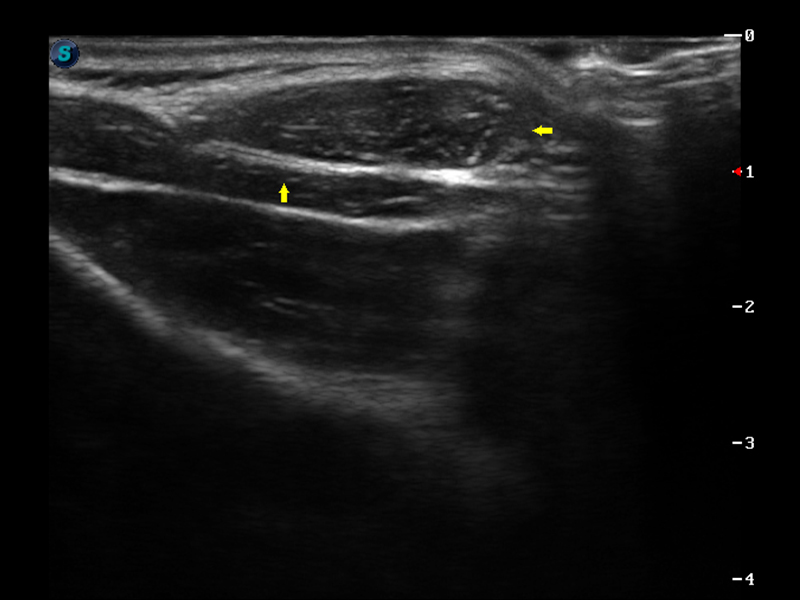

μ-Scan微米成像